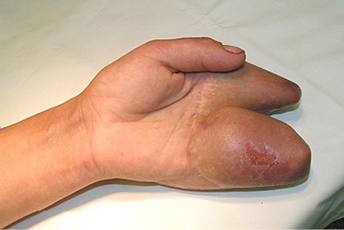

Priekinė ir šoninė kairės plaštakos rentgenograma. Stebimi II ir V pirštų kauliniai defektai per proksimalinį interfalanginį sąnarį (3 ir 4 pav.)